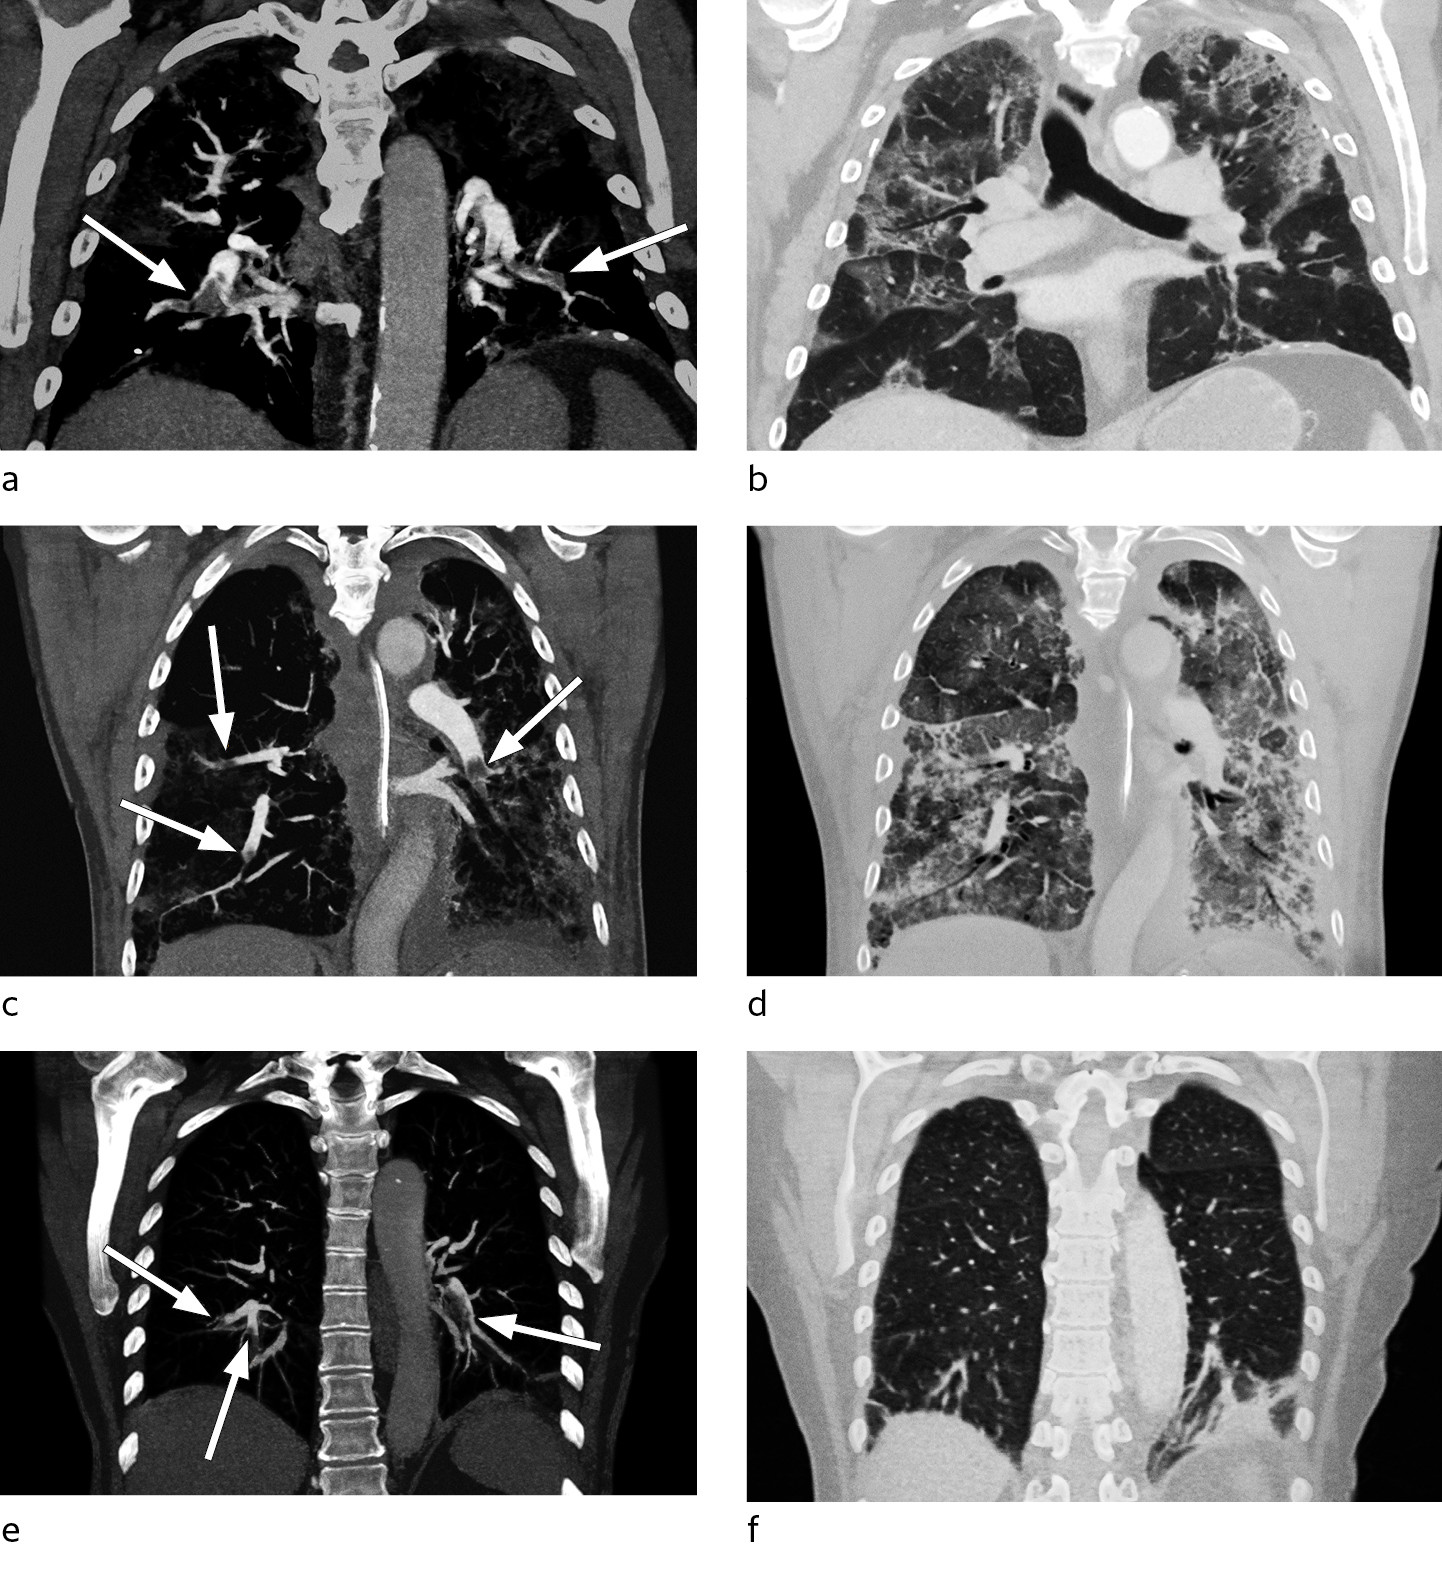

Han hadde økende oksygenbehov fra dag 9, med behov for 10 l/min på reservoarmaske for å holde SpO2 > 94 %. Han ble gradvis mer medtatt og sliten. Røntgen thorax dag 12 viste vesentlig uendret utbredelse av lungefortetninger. Grunnet manglende bedring i oksygenering og vedvarende sterkt forhøyet D-dimer til verdier > 10 mg/l FEU (figur 1) ble det dag 15 utført CT pulmonal angiografi. Denne avdekket bilaterale segmentale og subsegmentale lungeemboluser, i tillegg til utbredte infeksiøse fortetninger (figur 2a-b). Etter oppstart av antikoagulasjonsbehandling (enoksaparin 100 mg × 2) ble oksygenbehovet gradvis redusert og allmenntilstanden raskt bedre.

Med bakgrunn i rapporter om økt forekomst av venøse tromboemboliske hendelser hos intensivpasienter med covid-19 valgte vi å øke profylaksedosen av enoksaparin til 40 mg × 2. Dag 7 steg D-dimerverdiene fra 2,8 til 24 mg/l FEU. Ferritinnivået var > 2 000 µg/ml, og man startet behandling med interleukin-1-reseptorantagonist (anakinra) dag 10. Fram til dag 13 så man radiologisk progrediering av lungefortetninger, mens D-dimerverdien falt etter oppstart av anakinra (figur 1). Grunnet ny D-dimerstigning fra 16 mg/l FEU til 26 mg/l FEU ble det dag 16 utført CT pulmonal angiografi. Man fant da bilaterale perifere lungeemboluser og utbredte fortetninger i alle lapper (figur 2c-d). Det ble startet antikoagulasjonsbehandling (enoksaparin 100 mg × 2), men etter et langvarig forløp med stasjonær alvorlig lungesvikt døde pasienten dag 22.

En tidligere frisk kvinne i 70-årene gjennomgikk en ukes sykdom med lett tørrhoste og øvre luftveissymptomer. Det ble påvist sars-CoV-2 i luftveissekret etter to dager. Etter en to ukers periode uten symptomer tilkom det på ny tørrhoste, og pasienten ble innlagt dag 23 dager etter symptomdebut med aktivitetsdyspné og takypné. Det forelå ved innkomst respiratorisk alkalose, og D-dimerverdien var 1,9 mg/l FEU. Røntgen thorax viste normale funn. Det ble utført CT pulmonal angiografi, som avdekket bilaterale segmentale og subsegmentale lungeemboluser med affeksjon av alle lungelapper, uten funn av infeksjonssuspekte fortetninger (figur 2e-f). Hun fikk peroral antikoagulasjonsbehandling (apiksaban 10 mg × 2) og ble utskrevet da hun var i bedring.